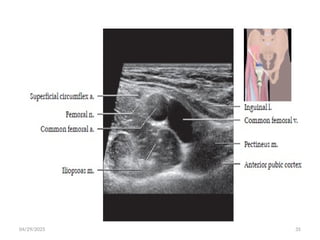

 Femoral Nerve

• Arises from posterior divisions of L2-L4 roots of the lumbar plexus.

• Largest branch of lumbar plexus.

• It emerges from the lateral boarder of the psoas muscle and medial boarder of

iliacus muscle.

• It sends motor branch to iliacus before passing under the inguinal ligament to

enter femoral triangle.

• Exits pelvis beneath inguinal ligament, lateral to femoral vessels, enters femoral

triangle.

Femoral triangle

• Anatomical space in the anterior upper thigh that contains

several structures.

 The boundaries are:

• Laterally medial border of Sartorius

• Medially medial border of adductor longus

• Superiorly inguinal ligament

• Floor ilopsoas laterally and pectineus medially

• Roof skin and subcutaneous tissue